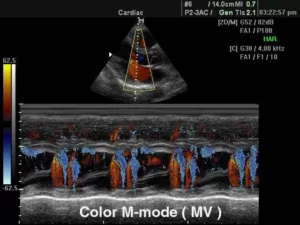

М-режим (отраженный импульсный режим)

M-mode («motion» — движение) — одномерная регистрация отраженного эхосигнала, применяющаяся в кардиологии для изучения сократительной способности миокарда, клапанного аппарата, оценки изменения размеров полостей в систолическую и диастолическую фазы.

В данном режиме оператор сканирует кардиальные структуры только вдоль одной оси. Информация о сигналах с различных глубин изображается в виде отметок различной яркости вдоль вертикальной линии на дисплее. Следующему зондированию соответствует другая линия, расположенная правее предыдущей. В ходе перемещения столбца с каждым новым сканированием записывается двухмерная М-эхограмма.

Существует несколько типов М-режима:

·      M-mode (стандартный): предполагает получение одномерного изображения;

9.jpg

·      Color M-mode (цветной): сочетает стандартный режим и цветовое допплеровское картирование;

11.jpg

·      Free-angle M-mode (анатомический): позволяет произвольно выставлять направление зондирования и визуализировать кардиальные структуры под различным углом.

12.jpg

При неправильном расположении курсора все параметры могут быть завышены, что приведет к неправильной интерпретации полученных данных. Поэтому диагностика в М-режиме требует строгого соблюдения правильной позиции сканирования.

Классический М-режим имеется во всех современных ИЗИ аппаратах, анатомический режим представлен в устройствах более высокого класса. Специальные датчики для обследования в М-режиме не применяются, регистрация М-эхограмм осуществляется датчиками для В-сканирования.